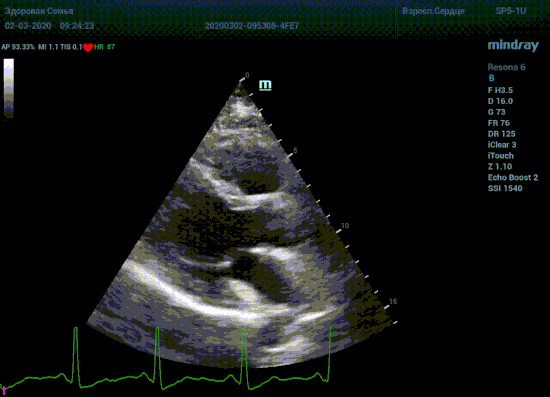

Подбор подобающей терапии и оценка её динамики на базе расчета массы миокарды рутинная задача эхокардиографии. Для измерения массы нужен кадр конца диастолы. На глазок или точно, по ЭКГ каналу, выбрать диастолу? Гипертрофия миокарда или его ремоделирование? Ремоделирование или норма? Решает каждый измеренный миллиметр, даже каждая его десятая. Лишние доли секунды приведут к началу сокращения миокарда и его утолщению, в результате -гипердиагностика.